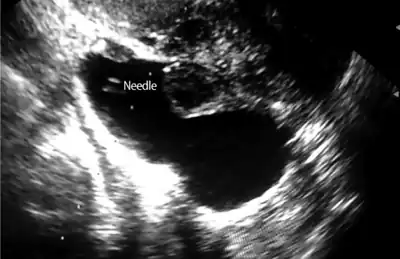

Needle in left hydrosalpinx to aspirate hydrosalpinx fluid.

Hydrosalpinx may be diagnosed using ultrasonography as the fluid filled elongated and distended tubes display their typical echolucent pattern. However, a small hydrosalpinx may be missed by sonography. During an infertility work-up a hysterosalpingogram, an X-ray procedure that uses a contrast agent to image the Fallopian tubes, shows the retort-like shape of the distended tubes and the absence of spillage of the dye into the peritoneum. If, however, there is a tubal occlusion at the utero-tubal junction, a hydrosalpinx may go undetected. When a hydrosalpinx is detected by a hysterosalpingogram it is prudent to administer antibiotics to reduce the risk of reactivation of an inflammatory process.